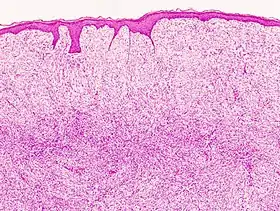

غالبا في كثير من الحالات يتم التشخيص الخاطئ للمرض على انه كيس دهن أو ما شابه وعلى انه ورم حميد وذلك التشخيص الخاطئ يجعل المريض يتجاهل الورم لسنوات عديده مما يزيد من حجم الورم. يمكن عن طريق التصوير بالرنين المغناطيسى (MRI) الكشف عن وجود الأورام، وللتأكد من التشخيص يمكن أخذ عينة من الورم عن طريق إبرة أو شق جراحي وفحصها تحت الميكروسكوب.[4]

البنية الضفيرية للورم

يتكون الورم من خلايا ليفية يافعة ومنسجات.

صبغة مناعية إيجابية لCD34